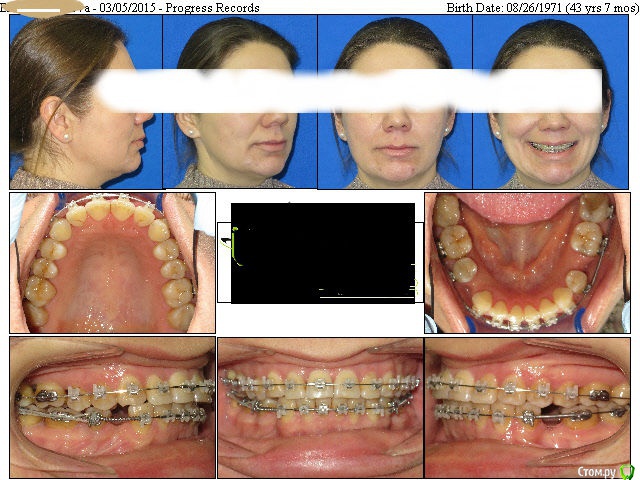

elena1971 Опубликовано 22 апреля, 2015 Автор Поделиться Опубликовано 22 апреля, 2015 После 7 месяцев болезненных ощущений сходила на консультацию к другому ортодонту. Врач сказал, что некоторые брекеты спозиционированны неверно. Уважаемые ортодонты, посмотрите пожалуйста фото до и после 5.5 мес. лечения. Интересно Ваше мнение. Ссылка на комментарий

Yana guapa Опубликовано 23 апреля, 2015 Поделиться Опубликовано 23 апреля, 2015 После 7 месяцев болезненных ощущений сходила на консультацию к другому ортодонту. Врач сказал, что некоторые брекеты спозиционированны неверно. Уважаемые ортодонты, посмотрите пожалуйста фото до и после 5.5 мес. лечения. Интересно Ваше мнение. Вам клиника предоставляет такие фото после каждого посещения? места под импланты внизу, кажется по фото , что недостаточно, Ваш ортопед должен смотреть. Ссылка на комментарий

elena1971 Опубликовано 23 апреля, 2015 Автор Поделиться Опубликовано 23 апреля, 2015 Вам клиника предоставляет такие фото после каждого посещения? места под импланты внизу, кажется по фото , что недостаточно, Ваш ортопед должен смотреть. Нет, не после каждого посещения. Одно фото до установки брекетов, второе - через почти 6 месяцев лечения. До имплантов еще очень далеко. Вообще, я думаю о смене врача. 7 месяцев лечения - длительные болезненные ощущения, передние верхние зубы ушли вперед. Справа верхние зубы ударяются о нижние, непонятно что с центром. Все процедуры проводит гигиенист, врач только бегло смотрит. Гигиенист в процессе лечения делает ошибки (в последний раз гнутую дугу поставила неправильно, сместив значительно центр и изгиб дуги попал в замок). После пары дней сильной боли врач поставила дугу по центру. Но это только мое мнение, хотелось бы узнать мнение профессионала. Ссылка на комментарий

Yana guapa Опубликовано 23 апреля, 2015 Поделиться Опубликовано 23 апреля, 2015 Нет, не после каждого посещения. Одно фото до установки брекетов, второе - через почти 6 месяцев лечения. До имплантов еще очень далеко. Вообще, я думаю о смене врача. 7 месяцев лечения - длительные болезненные ощущения, передние верхние зубы ушли вперед. Справа верхние зубы ударяются о нижние, непонятно что с центром. Все процедуры проводит гигиенист, врач только бегло смотрит. Гигиенист в процессе лечения делает ошибки (в последний раз гнутую дугу поставила неправильно, сместив значительно центр и изгиб дуги попал в замок). После пары дней сильной боли врач поставила дугу по центру. Но это только мое мнение, хотелось бы узнать мнение профессионала. судя по первоначальным фото у Вас и до лечения "верхние зубы ударялись о нижние", кардинальной разницы в прикусе не видно. Какая основная цель ортодонтического лечения у Вас? создать место? если будут стоять просто раскрывающие пружины, то передние зубы и будут уходить вперед. чтобы этого не происходило, то нужно делать акцент на боковых участках, и именно боковые зубы смещать назад в большей степени, а передние вперед в меньшей степени. для этого хотя бы минивинты как дополнительная опора должны быть установлены, и применена многопетлевая техника. У Вас, судя по фото, ни того ни другого. Ссылка на комментарий